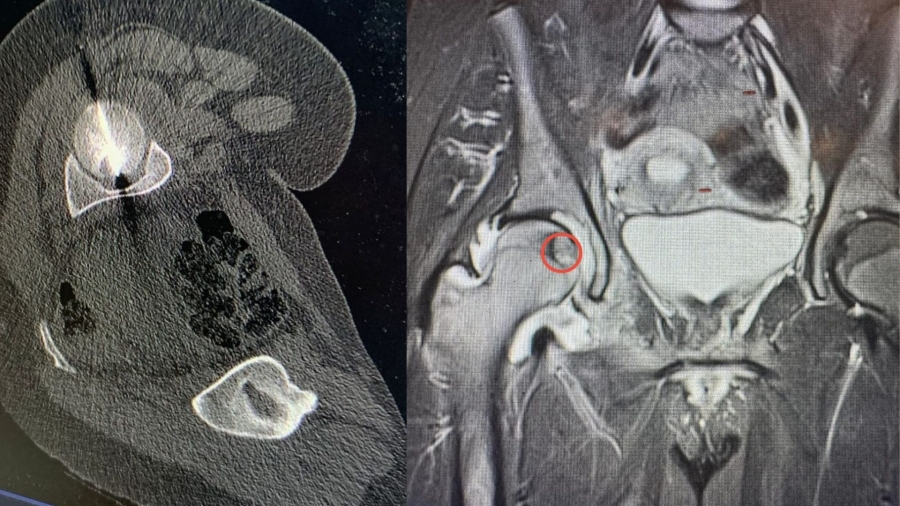

• أردنية عاشت 14 عاماً "أنثى" ثم تحوّلت إلى "ذكر".. ووالدها يناشد